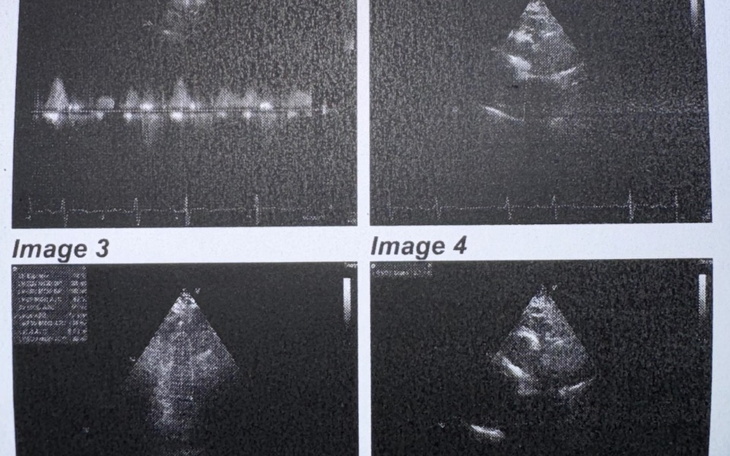

Cześć mam 20 lat, mieszkam w województwie dolnośląskim. Od zawsze uwielbiam pomagać innym, niestety nigdy nie sądziłam, że ja i moja rodzina będziemy potrzebowali tej pomocy. Na początku listopada dostaliśmy diagnozę, że tata ma tętniaka aorty wstępującej, który ma ponad 5cm. Do tego dochodzi nadciśnienie tętnicze oraz ekstrasystolia przedsionkowa i komorowa. Musi przejść operację przepukliny pępkowej. Na początku grudnia podczas angio-TK został wykryty rak tarczycy. Konieczne jest drogie leczenie. Będę ogromnie wdzięczna, za każdą złotówkę, a wszystkie zebrane pieniądze zostaną przekazane na leczenie mojego taty, który bardzo się męczy, a także boi się, że choroba odbierze mu życie. Dziękuję każdemu, kto zdecyduje się pomóc. Jestem ogromnie wdzięczna.